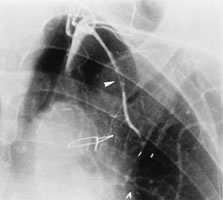

手術直後に造影した内胸動脈です。矢印部位で血管損傷が起こり、途中で血流が無くなっています。幸い、患者さんの症状が落ち着いていたので、経過を見ていました。そして一年後のことです。

一年後の造影では損傷して流れなくなった内胸動脈が見事に流れています。内胸動脈には「自己修復力」があるのだと思います。他の血管ではあまり無いことです。これを見た時は、本当に嬉しかったので、一生懸命英語の論文を書きました。論文を書いて投稿すると「査読」と言って専門家の先生が、評価をしてくれます。ダメ出しをされることも多いのです。この雑誌はアメリカの雑誌ですから、アメリカ人心臓外科医数人に査読して頂いています。皆さん、掲載にO.K.で高評価だったのですが、一人の先生は「こういう現象(内胸動脈の自己修復力)は自分でも数例経験している。珍しいことでは無い。でも論文になるのは初めてだ」と書いてきました。自分たちも似たような経験があったのでしょう。でも、書いたモノ勝ちですから、掲載してくれました。嬉しい出来事でした。